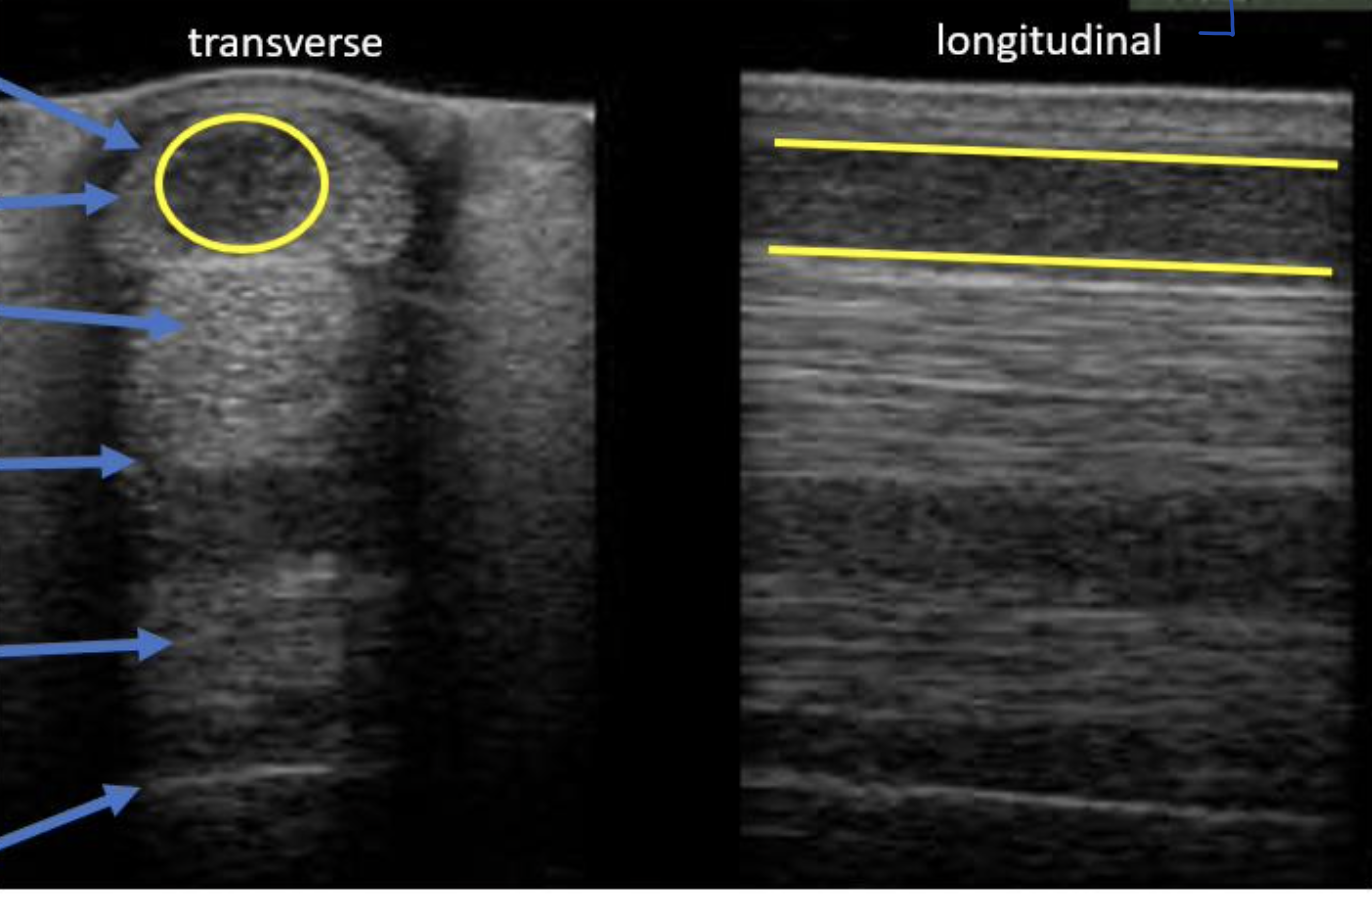

What are the 2 types of ultrasound probes/transducers?

Linear

Curvilinear (sector)

What ultrasound probe is most commonly used for equine tendons?

Linear Probe

What ultrasound probe is most commonly used for LA/SA abdomen and thorax?

Curvilinear (sector) Probe